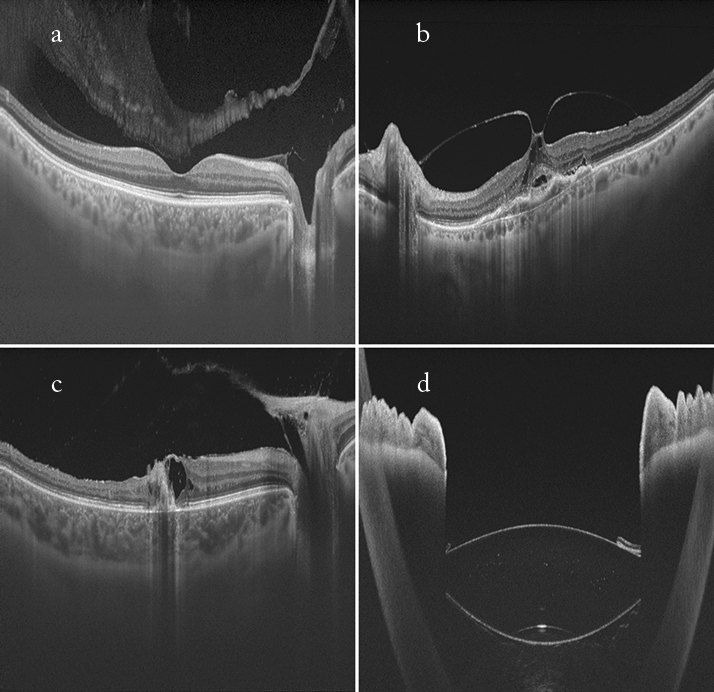

Tim Cole (a); Carl Glittenberg (b–d).

Swept source OCT images (Topcon DRI Atlantis). a. Healthy patient with a visible bursa premacularis in the vitreous above the macula, displaying clear definition of both the choroid and vitreous in one image. b. Vitreomacular traction syndrome (VMTS). Full extent of the VMTS is visible due to large scan width (12 mm). c. Vitreoretinal traction in a patient with posterior uveitis, with clear definition of the choroid and vitreous in one image. Again, the large scan width (12 mm) enabled the full extent of the lesion to be visualized. d. Iris and multifocal IOL: the swept source technology permits the large scan depth visualized.